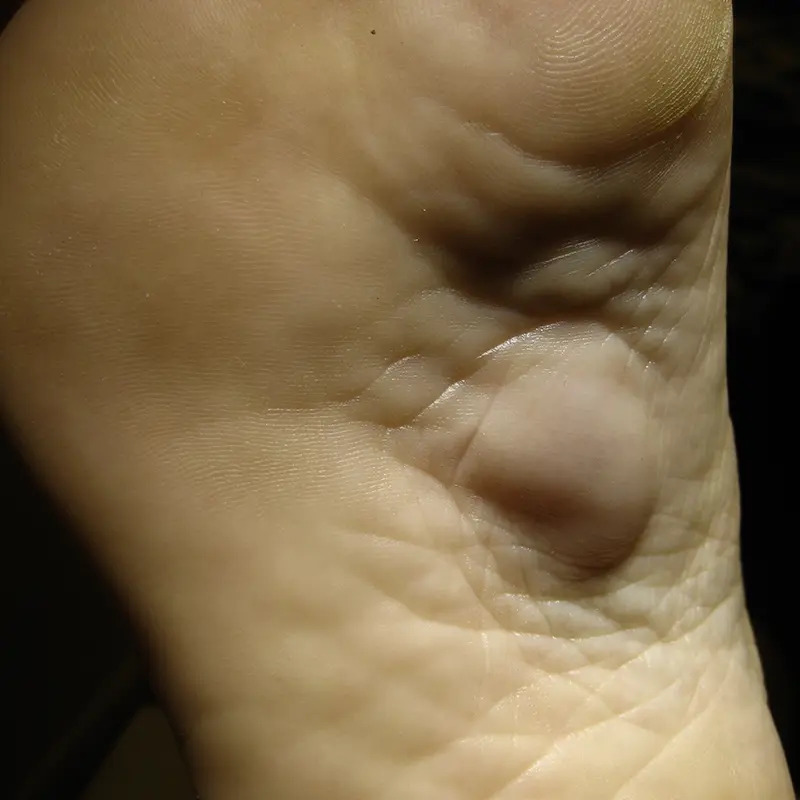

Cirugía de

los dedos y

lesiones locales

Algunas patologías afectan de forma muy localizada, pero no por ello son menos limitantes. Dolor al calzarse, roces constantes o infecciones repetidas suelen ser el motivo de consulta.

Dentro de este grupo se incluyen:

- Cirugía de uñas encarnadas (onicocriptosis).

- Cirugía de helomas (callos) y helomas interdigitales (ojo de gallo).

- Cirugía de partes blandas (quistes, lipomas, úlceras).

- Cirugía de exóstosis y osteocondromas.

- Cirugía de papilomas o verrugas plantares (multipunción, plastias, extirpación).

Son intervenciones que requieren una correcta indicación y un seguimiento adecuado para evitar recidivas y asegurar una buena recuperación.